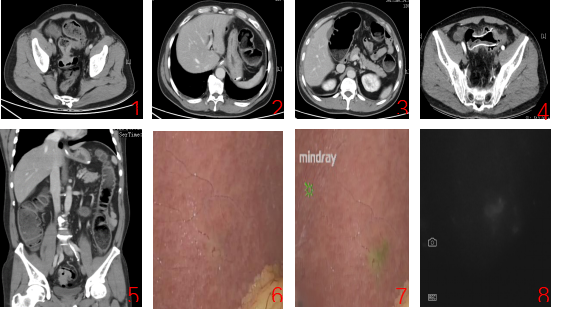

患者为中年男性,因急性肠梗阻入院,完善检查提示梗阻性乙状结肠癌合并肝转移。肝转移灶位于S3、S5段,为初始可切除病灶。患者腹痛腹胀明显,MDT讨论后制定先解除梗阻,后行转化治疗加手术的治疗方案。首先由消化内二科张健主任医师于肠镜下置入结肠支架,梗阻缓解,随后行转化治疗两周期。术前复查腹部CT及磁共振提示梗阻近端肠壁水肿减退,原发灶及肝转移灶明显缩小,可I期R0切除吻合。

患者肝转移灶直径约1.0cm,且位于不同肝段表面,经转化治疗后肝转移灶明显缩小,术中准确定位肝转移灶是手术根治的关键。吲哚菁绿荧光成像技术在肝脏肿瘤染色方面展现出重要临床价值,对距肝被膜小于8mm的结直肠癌肝转移病灶的敏感度为100%。结合患者情况及团队多年来在荧光导航腹腔镜技术方面的临床研究探索,术前经全科充分评估及讨论,为患者制定了荧光导航腹腔镜乙状结肠癌并肝转移I期同步切除术。

手术当天在手术二部及麻醉科通力协作下手术顺利进行,术中腔镜探查肉眼无法确认肝转移瘤部位,荧光模式下肝转移瘤清晰可见,随后行腹腔镜肝转移灶切除+乙状结肠癌根治,手术顺利,手术时长3小时,术后7天顺利出院。

1:乙状结肠肿瘤;2.肝S3段病灶;3.肝S5段病灶;4.结肠支架;5.冠状位显示肿瘤位置;6:非荧光模式下无法探及病灶;7:荧光模式下肝转移灶;8:荧光模式下肝转移灶